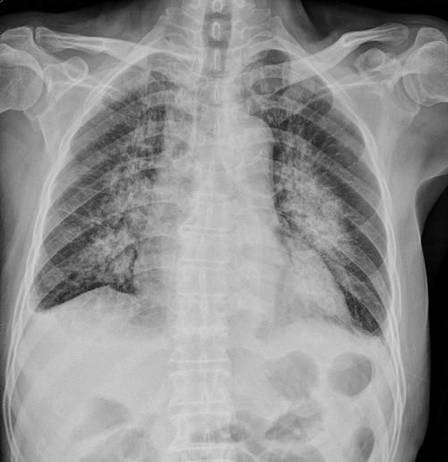

医生询问了小a被闷的整个过程后,预感小a可能是得了“蒙被综合症”,而且很可能有其他并发症,于是马上就给她拍了片。拍片的结果证实了医生的猜想:小a得了肺水肿。